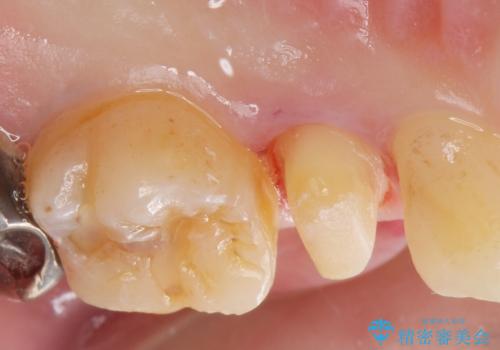

- 他院で被せた保険の白い被せ物(樹脂)をセラミックの被せ物に変えたいとの事で来院。

被せ物を外し、虫歯がないことを確認してセラミックの被せ物(ジルコニアクラウン)の治療を行いました。